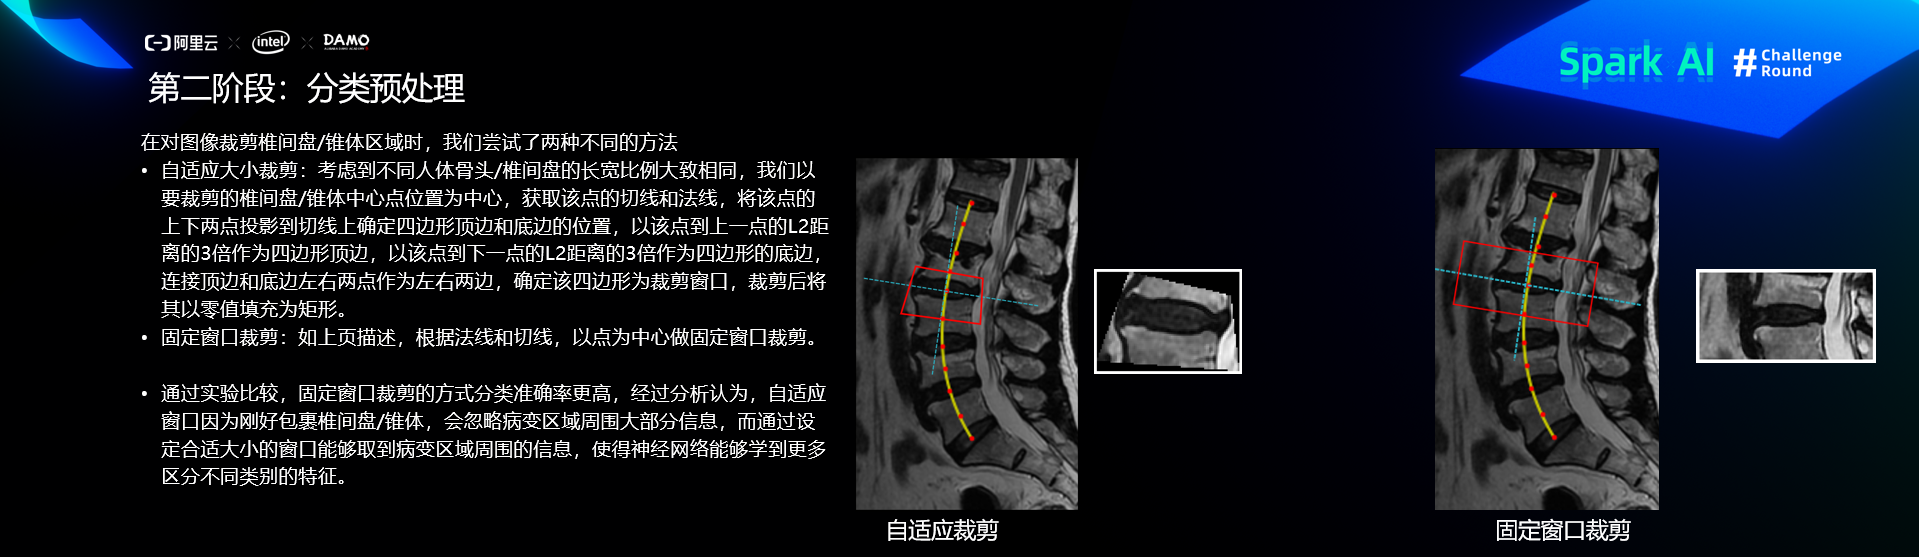

预处理